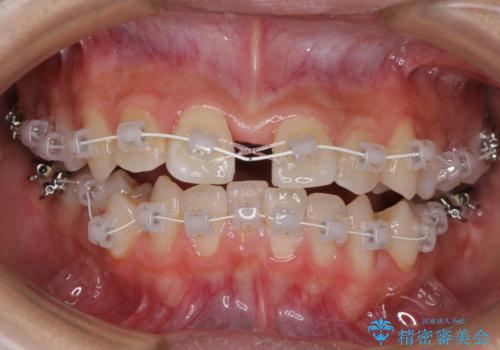

急速拡大装置を用いて上顎骨を側方に拡大し、上顎の叢生を解消するとともに下顎歯列拡大により下顎の叢生も解消することとしました。

急速拡大装置使用直後は著しいスペースが正中に発現するため、ワイヤー矯正を行いますが、今回は治療期間を短くしたいとのことで、上下全体をワイヤー装置にて矯正治療することとしました。